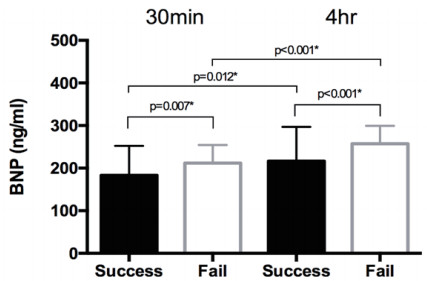

2.2 BNP及LAP对撤机的影响 2.2.1 BNP对撤机过程成功率的影响BNP检测结果提示撤机成功组在SBT 30 min后以及撤机后4 h的BNP水平均较失败组低(P < 0.01),且撤机过程失败组的BNP较成功组明显增加(P < 0.01)差异均有统计学意义。见图 3。

| 图 3 SBT 30 min BNP及撤机过程后4 h BNP(ng/ml)对比 |